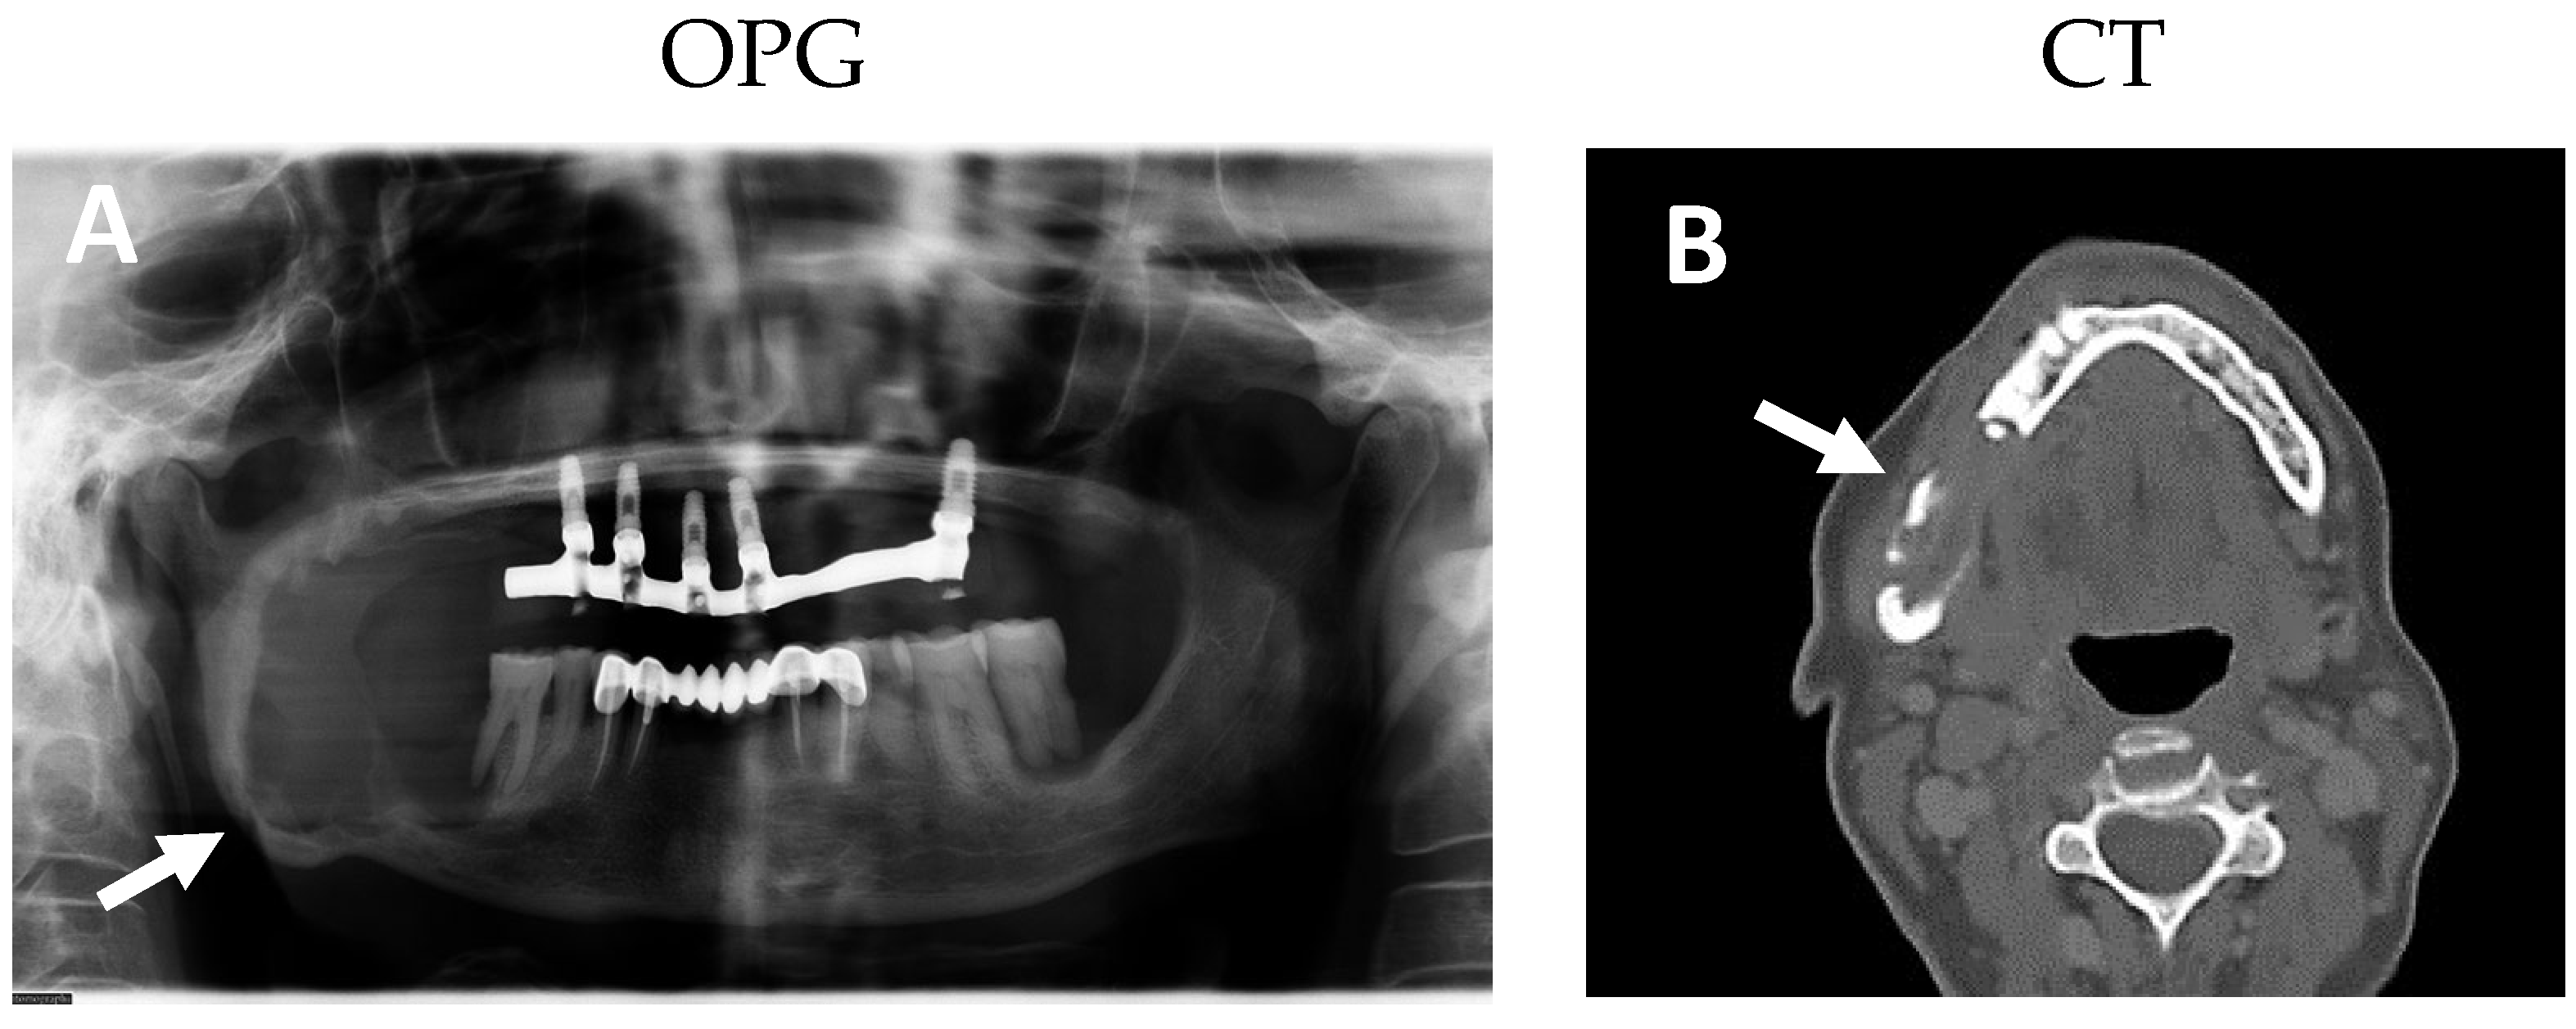

2.1. Clinical and Histological Manifestations of the Tumors